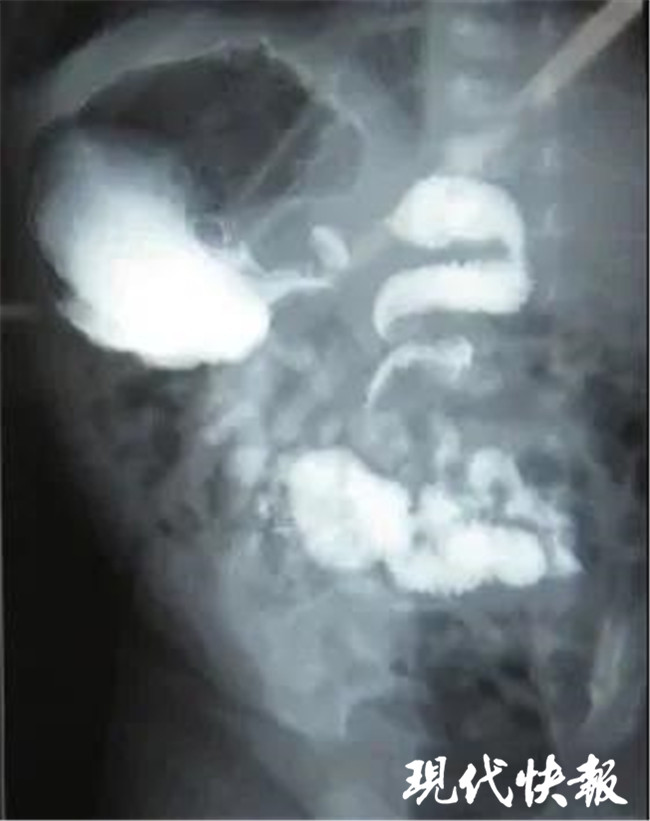

△先天性肠旋转不良 资料图片

“入院后造影检查发现,男孩的肠子呈“旋涡状”。本该位于右下腹的阑尾跑到了左下腹,这说明孩子的肠子扭转了。”南通市妇幼保健院小儿外科主任张友波介绍说,会诊后,随即安排孩子进行手术治疗。在急诊手术,医生发现孩子的小肠绕肠系膜根部顺时针旋转了360度,盲肠和升结肠也随之旋转,十二指肠黏连连受压,导致肠梗阻。